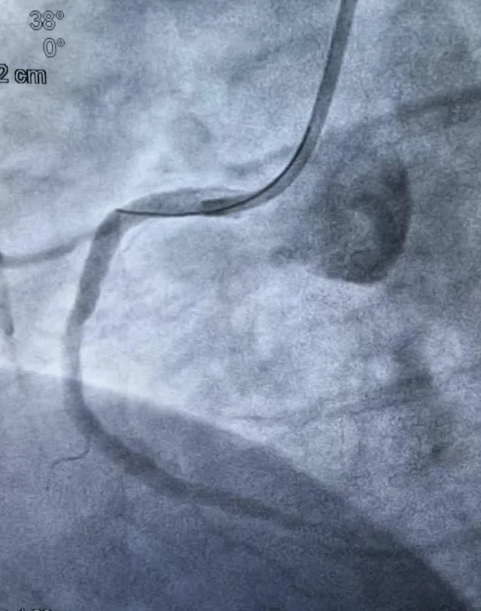

造影结果明确后,介入团队沉着应对,制定个体化方案,依次实施球囊扩张、血栓抽吸、冠脉内溶栓,精准清除血栓,解除血管闭塞,成功植入3枚支架,完全恢复冠脉血流,术后患者胸痛症状即刻缓解。